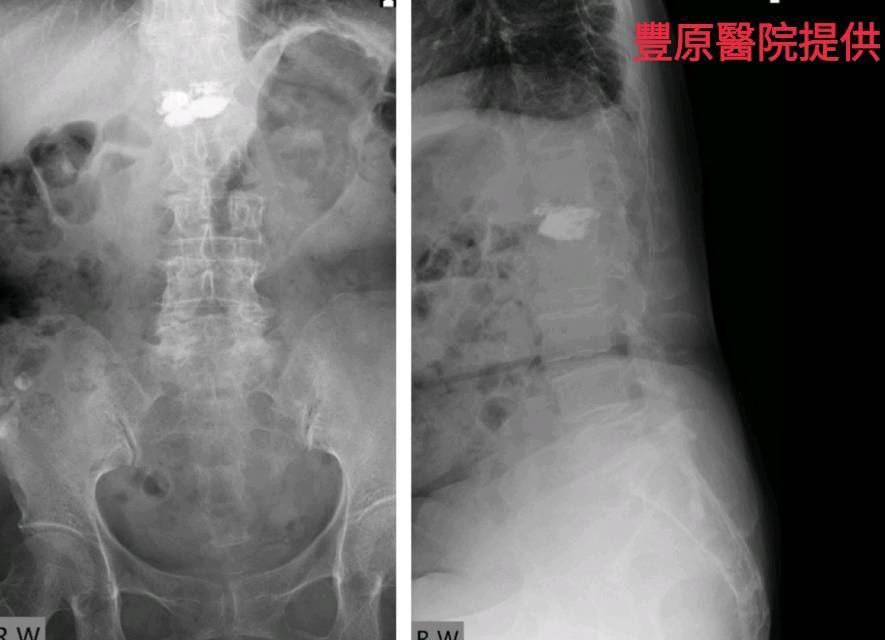

【記者于郁金/臺中報導】73歲曾姓女患者,練瑜珈有30多年,上個月卻因下背疼痛到骨科求診,醫師經X光檢查發現,患者的第一腰椎嚴重骨折,詢問下才得知,原來她是在瑜珈下課後自己練習高難度的「犁鋤式」動作,沒想到當時的「喀聲」竟是骨折聲。

豐原醫院骨科醫師江福財表示:瑜珈的「犁鋤式」動作,是將下肢整個雙腳屈膝上提,利用腹部肌群與骨盆力量,從尾椎開始慢慢將脊椎一節一節往上捲,將腿往頭頂做曲折,如果沒人在旁指導則容易受傷,患者才會導致胸、腰椎的交接處骨折。

一般人最常骨折的地方是在第一、第二腰椎處、和十、十一及十二胸椎處,以人體的脊椎結構來看,胸椎是一個前傾的角度、腰椎是一個後傾的角度,如果受傷最大常見的反應就是痛,嚴重者會壓迫到神經,導致下肢無力等情形。